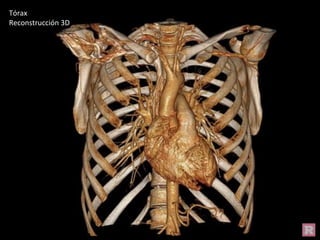

Tórax

Reconstrucción 3D